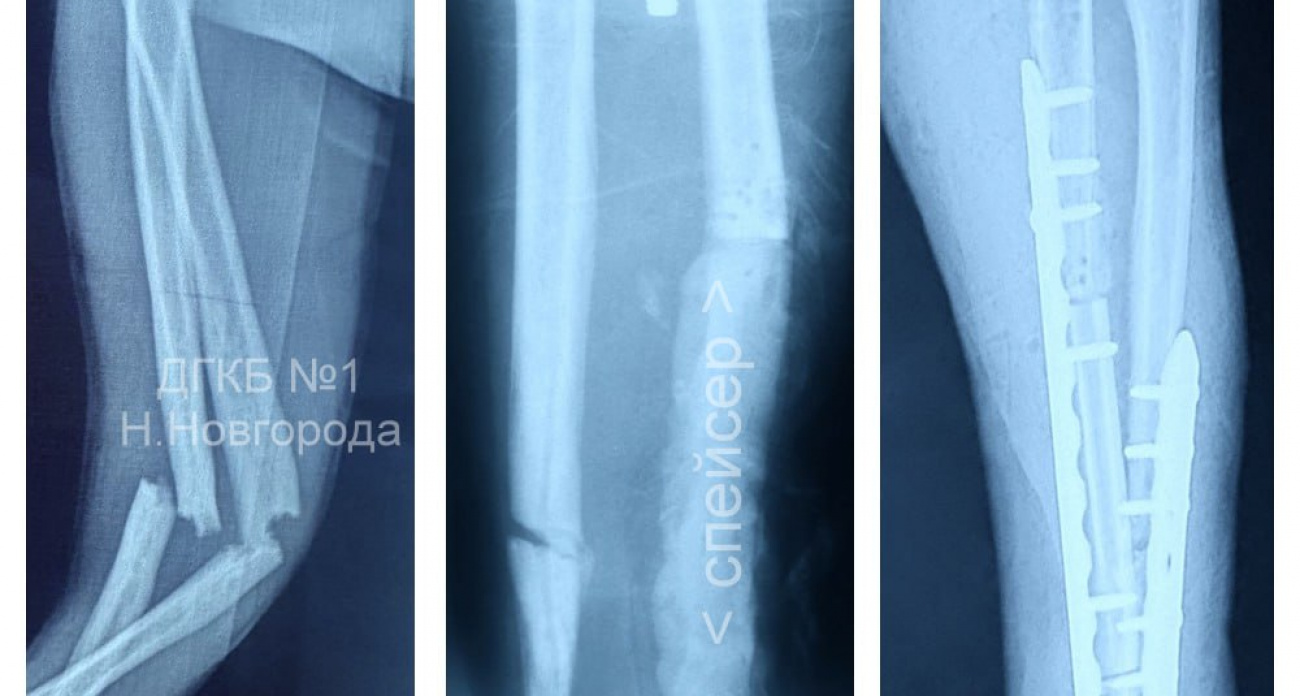

Изначально в зарубежной клинике диагностировали перелом обеих костей левой руки и сделали операцию, но через 10 дней появились гнойные осложнения. Вернувшись домой, ребенок попал в городскую детскую больницу № 1. Медики диагностировали уже воспаление костей предплечья.

Сначала врачи удалили около 9 сантиметров поврежденной кости, очистили очаг инфекции. Затем провели костную пластику. Для замещения дефекта использовали часть собственной малоберцовой кости пациента, распилили несросшуюся локтевую кость и зафиксировали обе сломанные кости пластинами. Врачи отмечают, что школьник уже выписан из больницы и вернулся к обычной жизни.